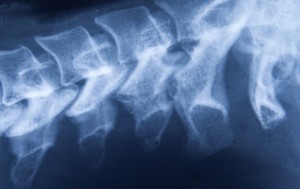

Harley Street Spine specialist highlights how good posture can improve other health conditions

Consultant surgeon to Harley Street Spine, Mr Bob Chatterjee, reveals that bad posture can be an indicator of health problems. He says, “Whilst there is a commonly held belief that posture represents confidence and greater self awareness, most do … Read more →